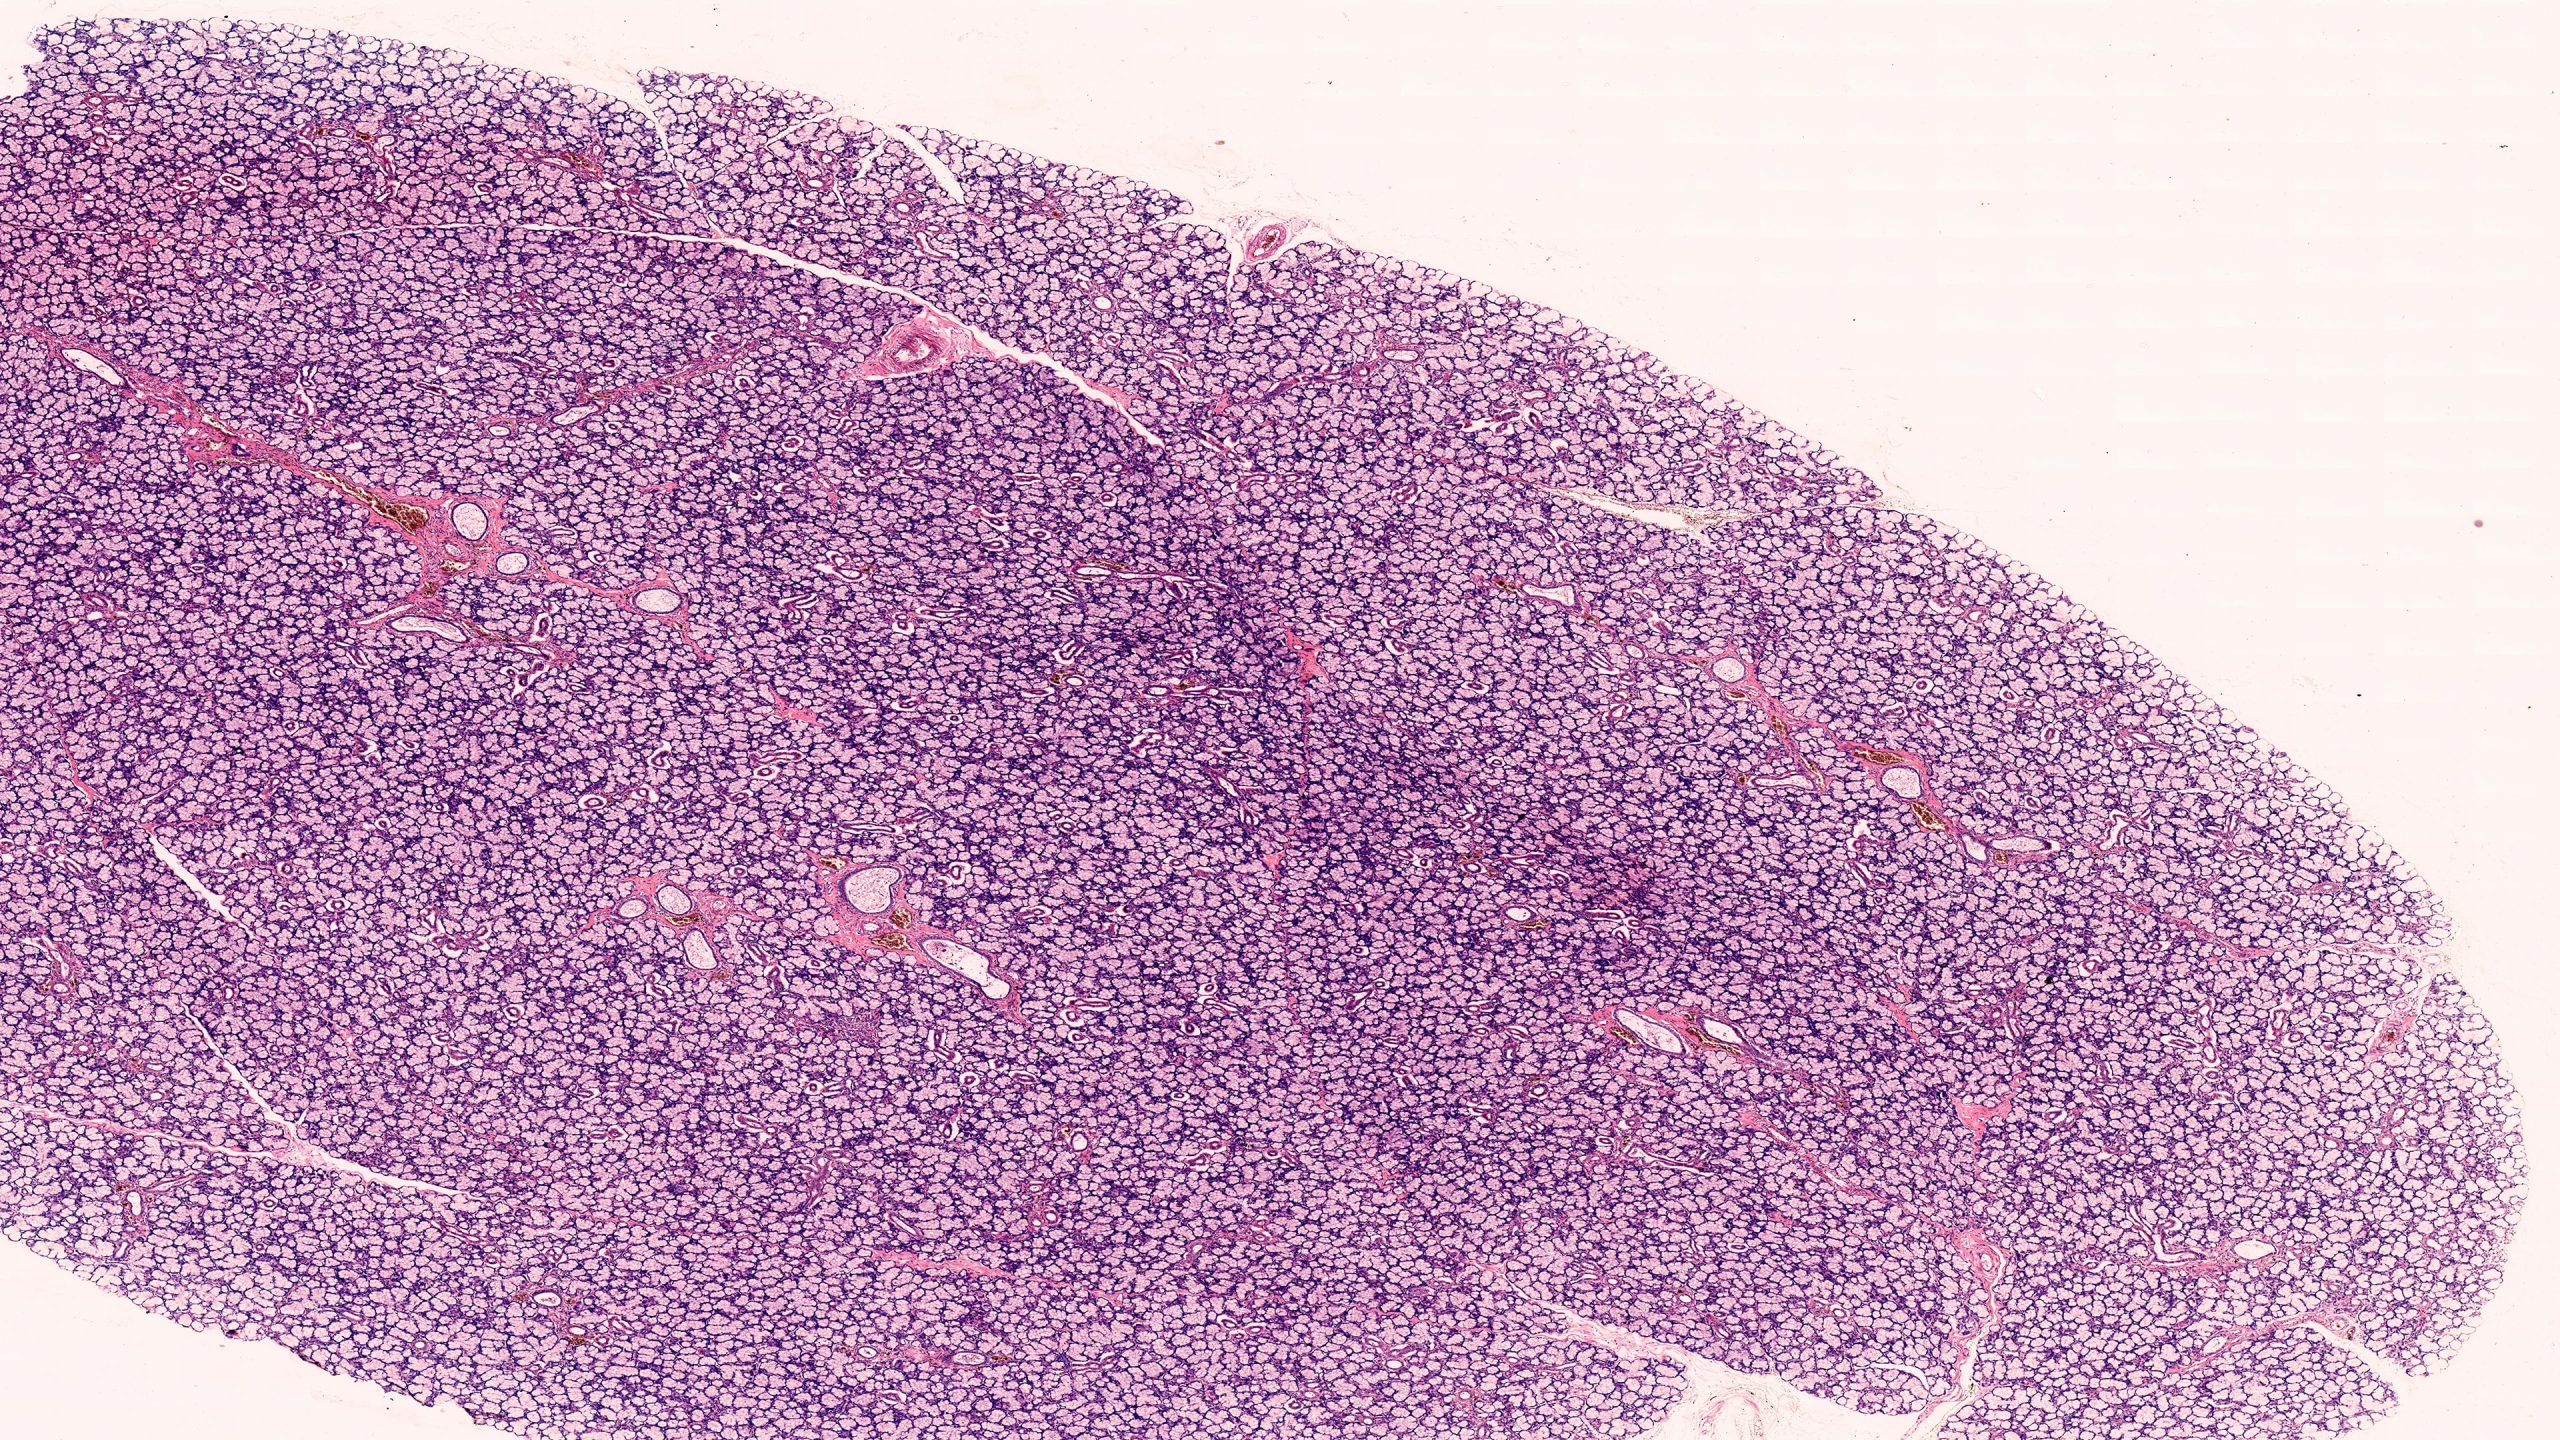

Mixed Salivary Gland 4X